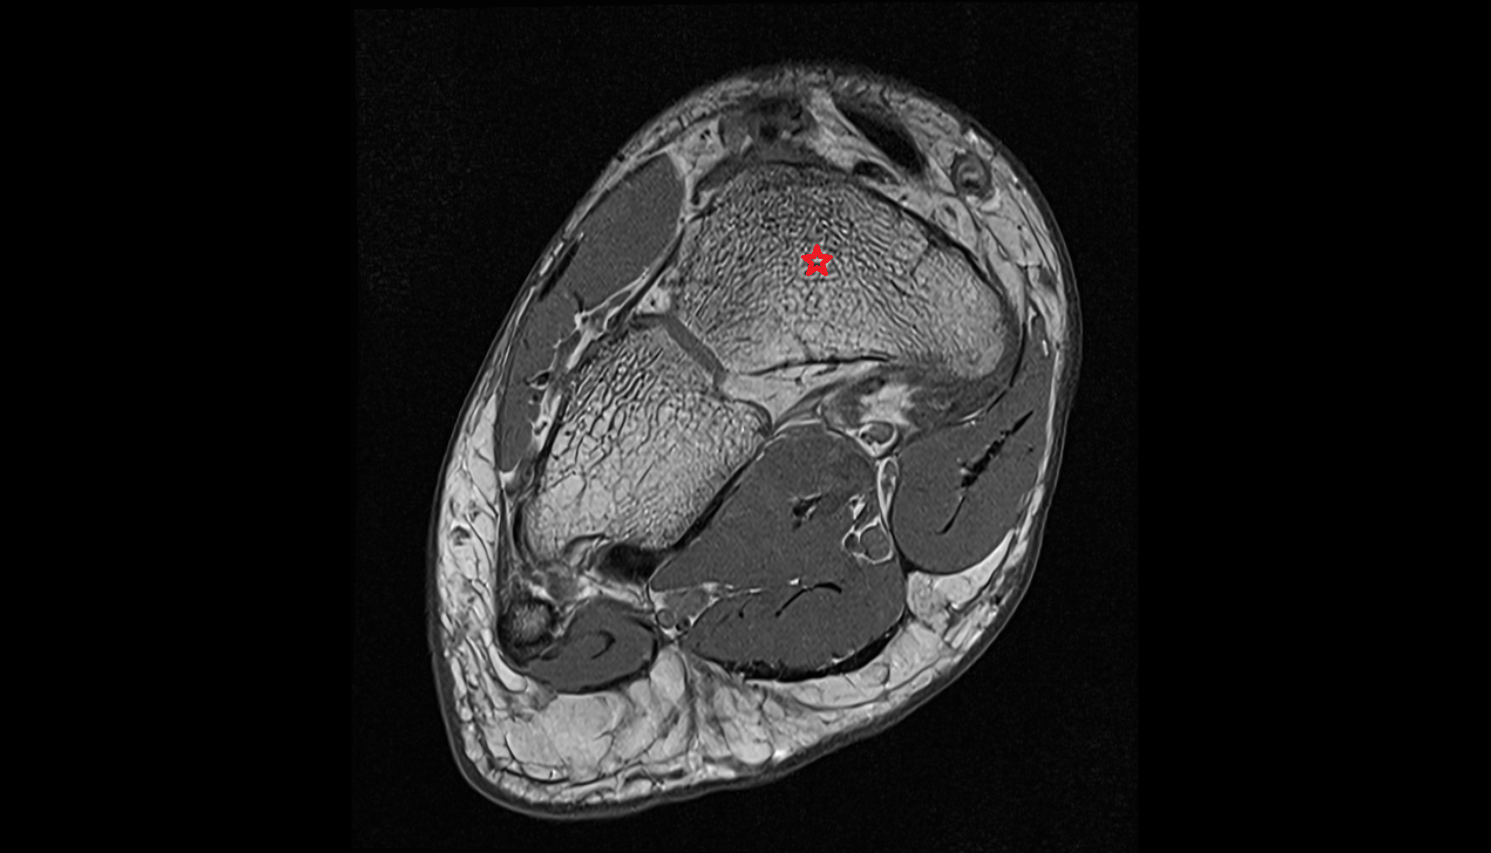

- Talus

- Body of talus

- Calcaneus

- Ankle joint

- Tibialis posterior muscle

- Flexor digitorum longus muscle

- Flexor hallucis longus muscle

- Quadratus plantae muscle

- Abductor hallucis muscle

- Flexor digitorum brevis muscle

- Abductor digiti minimi muscle

- Tibialis posterior tendon

- Flexor digitorum longus tendon

- Flexor hallucis longus tendon

- Achilles tendon